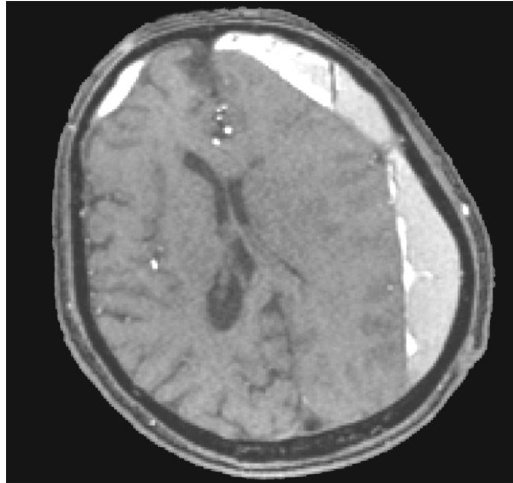

基于术前磁共振综合评估选择不同术式治疗慢性硬膜下血肿

Abstract : ObjectiveTo explore the efficacy of different surgical procedures for the treatment of chronic subdural hematoma(CSDH) based on comprehensive preoperative magnetic resonance evaluation. MethodsAll235 patients with CSDH who underwent surgery at the Jiangyin Clinical Collge of Xuzhou Medical University between June 2O2O and June 2O24 were analyzed.All patients underwent routine MRI and MRA examinations prior to surgery to assess hematoma cavity separation,neovascularization,and middle meningeal artery(MMA)dilatation.Diferent surgical approaches were adopted based on the results of the imaging assessment. Patients were followed up for 6 months postoperatively to observe improvements in clinical symptoms and signs,as well as postoperative recurrence rates. ResultsThe overall recurrence rate was 4.7% .The postoperative complication rates were 4.2% for wound infection, 17% for intracranial pneumatocele,and 4.2% for epilepsy. ConclusionsBased on comprehensive preoperative MRI assessment,individualized selection of different surgical procedures for the treatment of CSDH can reduce the postoperative recurrence rate and improve patient prognosis.

慢性硬膜下血肿(chronic subdural hematoma,CSDH)是颅脑损伤后导致颅内出血的常见形式之一,体液、血液和血液降解产物的集合积聚在脑表面蛛网膜和硬脑膜覆盖物之间,形成慢性占位性病变[1]。(剩余10833字)